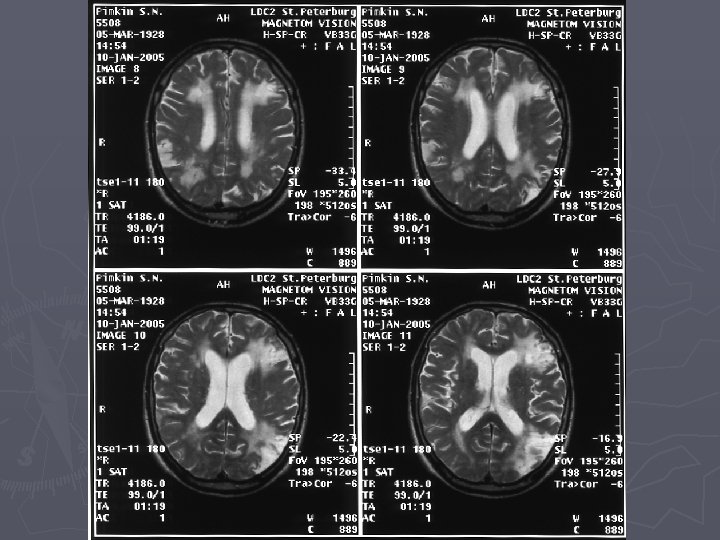

Инструментальные методы исследования ► КТ характеристики претерпевают динамику от минимальных атрофических изменений мозга в 1 стадии ► к мелкоочаговым изменениям вещества ГМ и атрофическим (наружным и внутренним) проявлениям во 2 стадии ► до резко обозначенной корковой атрофии и гидроцефалии с множественными гиподенсивными очагами в полушариях – в 3 стадии